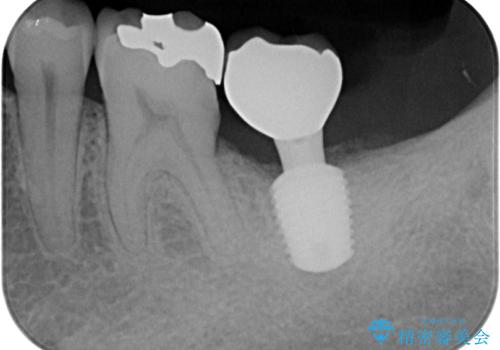

左下の奥歯は状態が非常に悪く、保存は困難と判断されたため、インプラントによる補綴治療が必要でした。

上顎左右の歯をアンカースクリューを用いた部分矯正により位置を修正し、オールセラミッククラウンにて補綴治療を行うこととしました。

矯正治療に時間はかかりましたが、外側に飛び出した歯が内側に収まったことで、非常に歯が磨きやすくなったとのことでした。